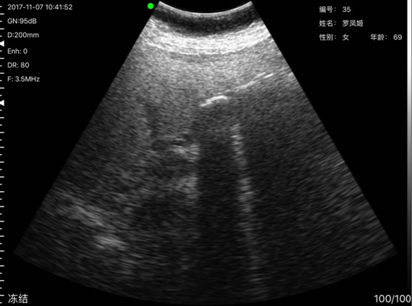

病例7,姓名:罗x姬,性别:女,年龄69岁,发现其胆囊有两亮点疑似胆囊结石,后经上级医院复查确诊为胆囊结石。

胆囊结石与上级医院复诊结果一致

胆囊结石